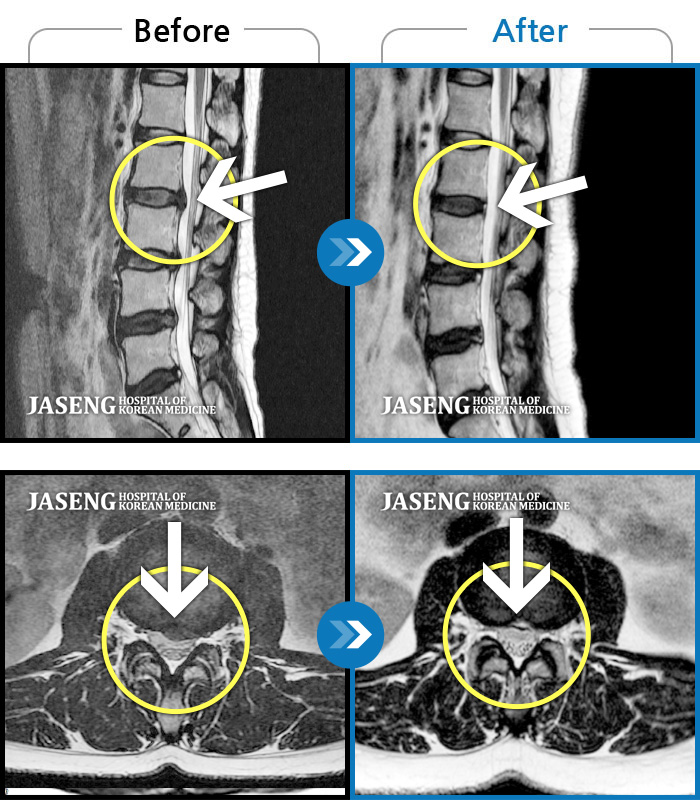

허리디스크

강남 · 강만호 원장

허리통증 및 왼쪽 다리 통증으로 운전이 불가능했습니다.

촬영시기

2023.10.16 ~ 2024.10.14

2024.10.23